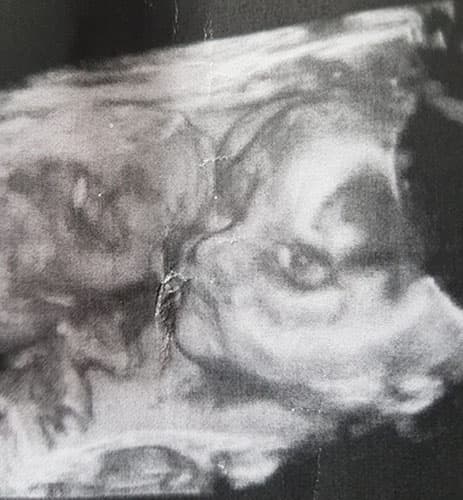

Ultraschallbilder aus dem 3. Trimester (29. bis 40. SSW)

Im dritten Trimester der Schwangerschaft ist das Baby so groß, dass es nicht mehr komplett auf ein Ultraschallbild passt. Nun kann man wunderbare 3D-Ultraschalle des Gesichts machen. In diesem Semester nehmen die Babys nochmal rasant zu und wer Glück hat, kann auf seinem Ultraschall schon erste Gesichtszüge erkennen.

Was genau man auf einem Ultraschallbild erkennen kann, hängt nicht nur von der Größe des Babys ab, sondern auch davon wie gut das Ultraschall-Gerät ist, mit dem die Aufnahme gemacht wurde. Auch auf den Ultraschallbildern hier kannst du sehen, dass die Qualität stark schwankt. In der Regel kann man gut den Kopf und RUmpf des Babys erkennen und auch die Gliedmaßen erkennt man selbst als Laie gut.

Wer sich jedoch erhofft Gesichtszüge zu erkennen, der wird oft enttäuscht. Zwar kann man beim 3D-Ultraschall schon eine Menge sehen, aber das umgebende Fruchtwasser sorgt in den allermeisten Fällen für starke Störungen.